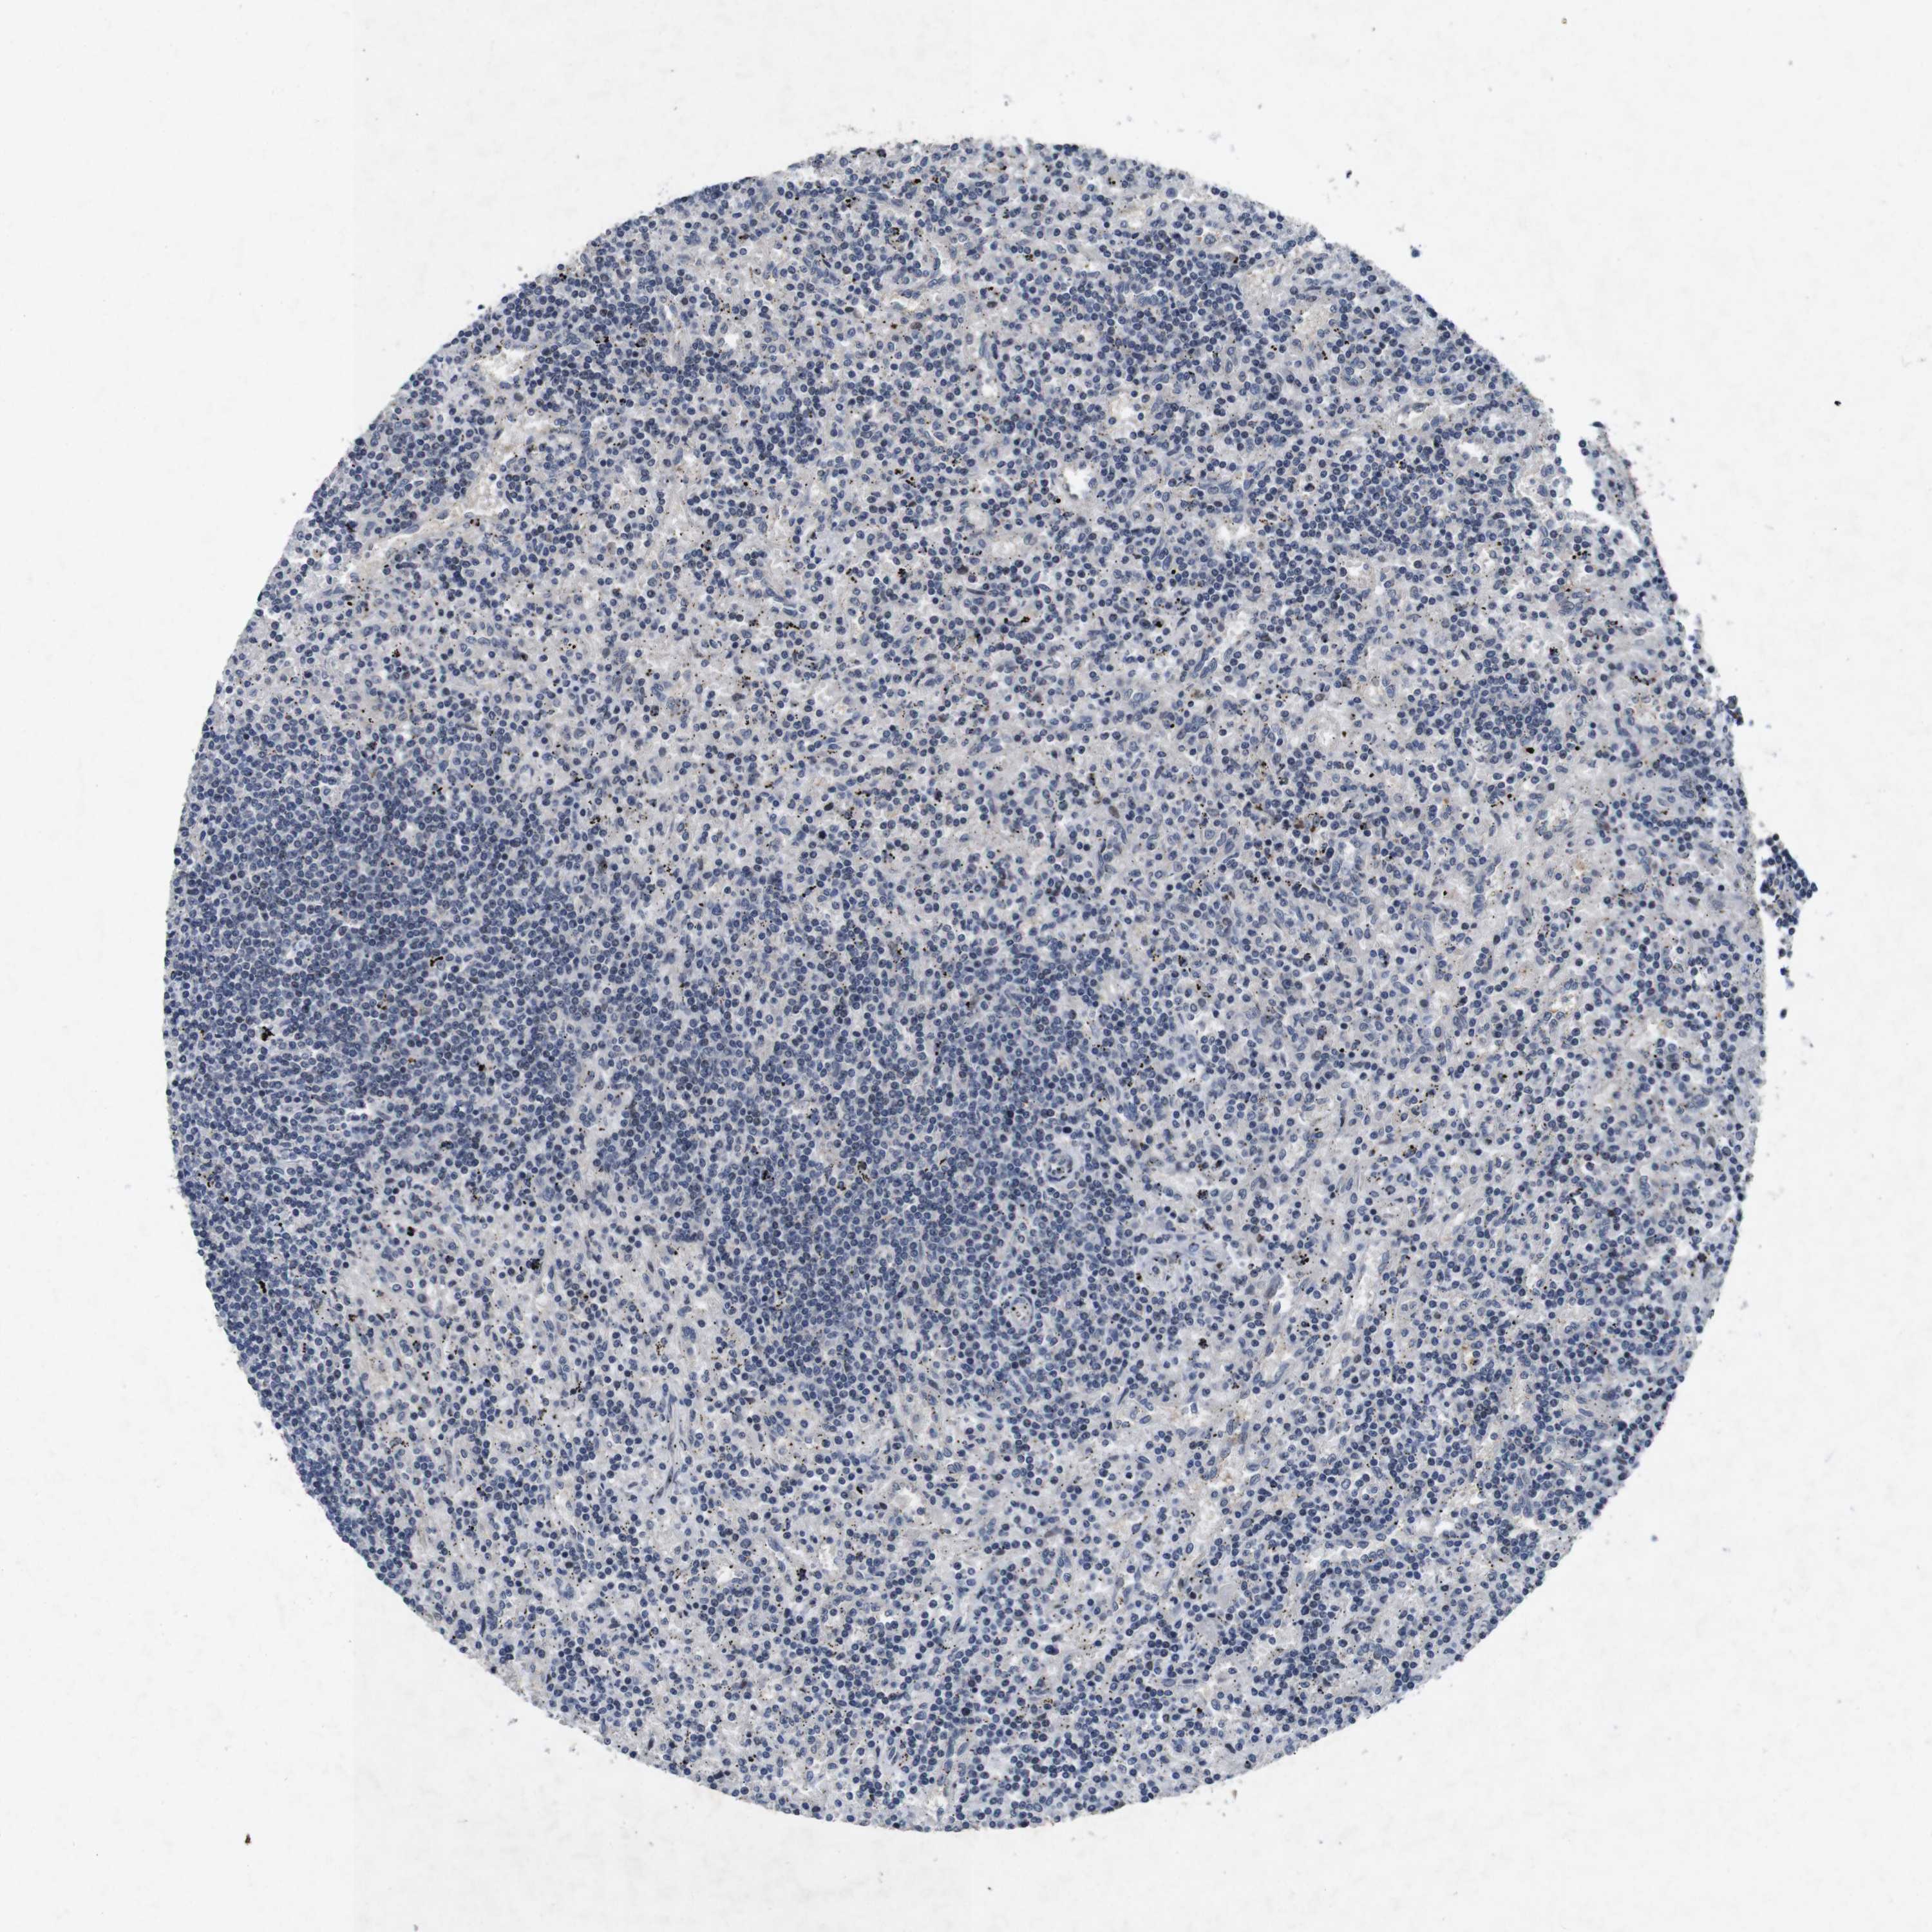

CANCER LYMPHOMA Show tissue menu

LYMPHOMA - Protein expressioni

A mouse-over function shows sample information and annotation data. Click on an image to view it in a full screen mode. Samples can be filtered based on level of antibody staining by selecting one or several of the following categories: high, medium, low and not detected. The assay and annotation is described here.

Antibody stainingi

Antibody staining in the annotated cell types in the current human tissue is reported as not detected, low, medium, or high, based on conventional immunohistochemistry profiling in selected tissues. This score is based on the combination of the staining intensity and fraction of stained cells.

Each image is clickable and will lead to virtual microscopy that enables deeper exploration of all samples and also displays staining intensity scores, fraction scores and subcellular localization as well as patient and tissue information for each sample.

Antibody HPA026441

Antibody CAB013090

Staining

High

Medium

Low

Not detected

Intensity

Strong

Moderate

Weak

Negative

Quantity

>75%

75%-25%

<25%

None

Location

Nuclear

Cytoplasmic/membranous

Cytoplasmic/membranous,nuclear

Hodgkin's disease, NOS

Malignant lymphoma, non-Hodgkin's type, High grade

Malignant lymphoma, non-Hodgkin's type, Low grade